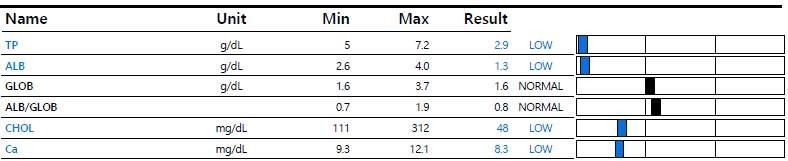

[혈액 검사]